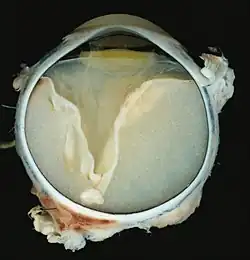

La enfermedad de Coats ( sinónimo de retinitis exudativa y telangiectasia retiniana ) es un proceso crónico que comienza a manifestarse en la juventud o niñez y que se desarrolla de forma lenta y progresiva. Está causada por un desarrollo anormal de los vasos sanguíneos de la retina (la capa más interna del ojo sensible a la luz). Conduce a una pérdida significativa de visión.

Es una enfermedad poco frecuente que afecta más a los varones que a las mujeres, el 80% de los pacientes presentan síntomas antes de los 10 años. Las manifestaciones iniciales consisten generalmente en pérdida de visión unilateral, pues la enfermedad suele afectar solamente a un ojo. También puede producirse estrabismo y en las fases avanzadas, manifestaciones más graves, como desprendimiento de retina. Debido a la alteración de los vasos sanguíneos de la retina, se producen exudados amarillentos que son visibles mediante la exploración del ojo con un oftalmoscopio. Es una de las patologías con las que hay que hacer diagnóstico diferencial de leucocoria. Si estos exudados afectan a la mácula (la porción central y más sensible de la retina), la pérdida de capacidad visual es muy importante. Otras veces se produce una complicación grave que se conoce como edema macular.